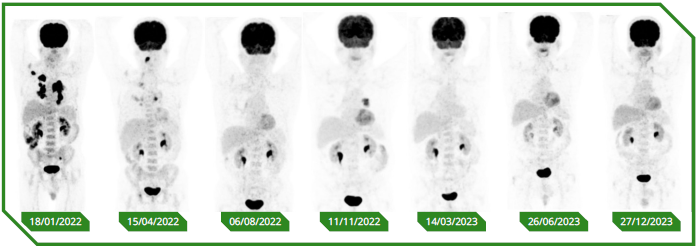

Paciente masculino de 65 anos, previamente sem comorbidades, diagnosticado com carcinoma espinocelular de língua, tratado inicialmente com cirurgia e radioterapia adjuvante, evoluindo precocemente com doença metastática pulmonar e óssea. No momento da avaliação oncológica, apresentava performance status comprometido e alta expressão de PD‑L1 (CPS 30). Optou-se por imunoterapia isolada em primeira linha, considerando perfil clínico e objetivo de redução de toxicidade, com acompanhamento longitudinal e intervenções locais conforme necessidade.